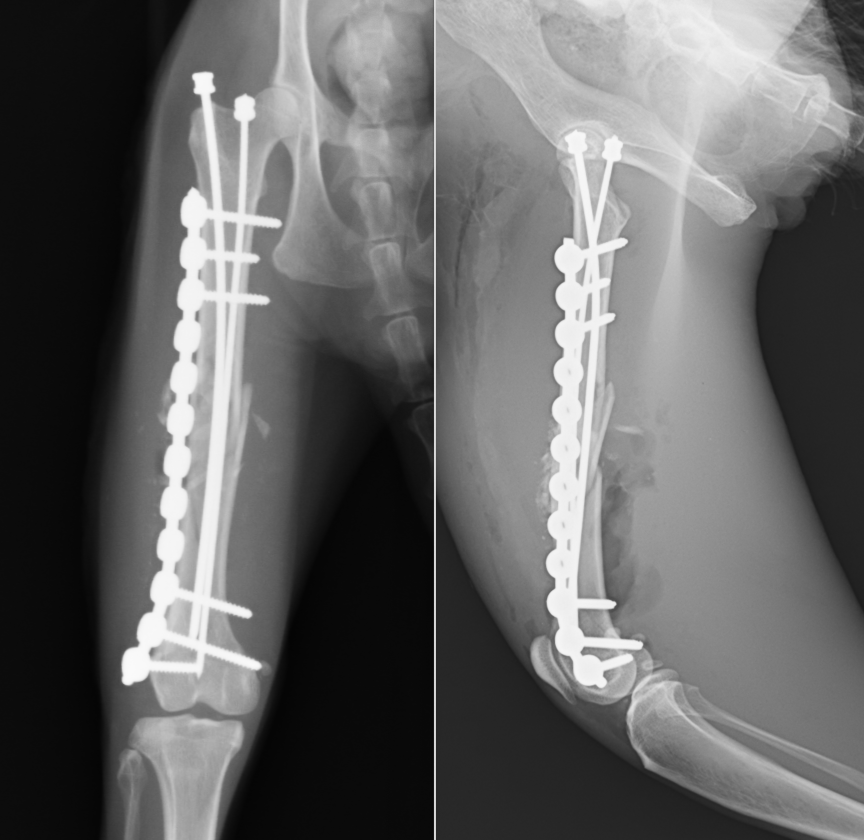

老齢猫の大腿骨骨幹部中央の斜骨折です。老齢猫では骨が固く、もろくなっていくので簡単に骨が割れていくことがあります。

なるべくそうならないよう髄内ピンを設置してからプレート設置を行いましたが、それでも数箇所割れてしまったところがあります。SOPプレートというロッキングプレートの一種で固定しています。老齢のため、骨化を促進するためフリーズドライのパウダーを入れています(写真右)

術後レントゲンです。アライメント(向きや配置)も問題なく固定されています。術後すぐに歩きだし、3週後には走り回って、家を脱走するくらいとのことでした。